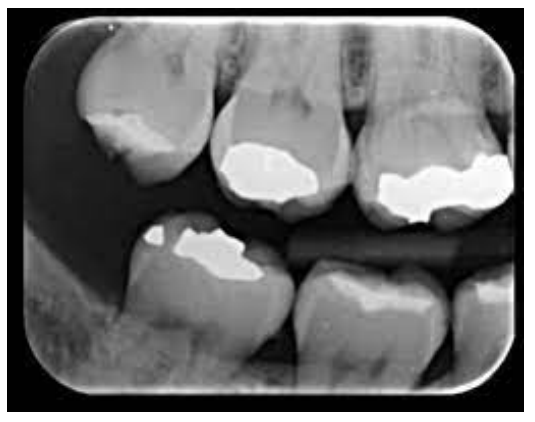

Para correta montagem de radiografias odontológicas, é necessário o conhecimento do tipo de radiografia, dos elementos dentais e o seu posicionamento.

A radiografia ilustrada acima refere-se a uma: